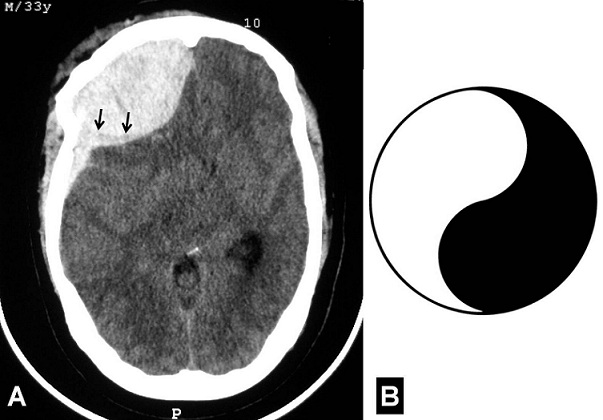

The yin-yang shaped image following head injury

A 33-year-old previously healthy man was admitted with a craniofacial trauma sustained in a road traffic accident. No post-traumatic seizures were documented. On physical examination, large wound was observed in the frontal region on the right side. He was comatose, and his consciousness level was 6 on the Glasgow Coma Scale. The right pupil was dilated but responsive to light. The axial slices of the cerebral computed tomography-scan (CT-scan) revealed a distorted right cerebral hemisphere with effacement of the basal cisterns, which was compressed by an extraaxial haematoma located in the right frontoparietal region. This haematoma was found to have two different components: the first (anterior) was epidural and the second (posterior) was subdural. Both haematomas were evacuated through a right frontoparietal craniotomy. Postoperatively, CT-scan showed no evidence of residual haematoma. The patient has been in good health throughout the 3-month follow-up since the accident. Classic CT-scan appearance of intracranial epidural haematoma (EDH) is high density biconvex shape adjacent to the skull and usually confined to small segment of calvaria. On the contrary, acute subdural haematoma (ASDH) appear more diffuse, less uniform, usually concave over brain surface and often less dense (from mixing with cerebrospinal fluid) than EDH. But when combined, these two different surgical entities are not easy to distinguish on CT-scan. The Yin-yang-shaped image seen in our patient is formed by an anterior biconvex shape and a posterior concave shape, the combination of adjacent epidural and acute subdural haematoma. The radiologic features of our presentation are interesting and might be useful to distinguish both adjacent EDH and ASDH.